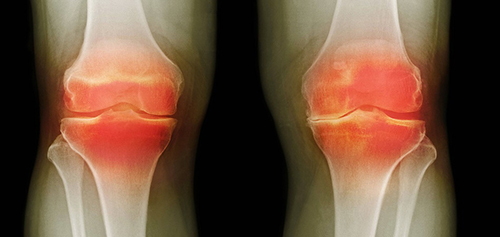

- แคลเซียมเกาะกระดูก (Osteophytes) คือตัวการของโรคข้อและกระดูกกว่า 97% เช่น โรคข้ออักเสบ โรคข้อเสื่อม โรคกระดูกอ่อน โรคกระดูกพรุน โรคไขข้ออักเสบ โรคถุงน้ำในข้ออักเสบ และแม้แต่ซีสต์ของปมประสาท

เมื่อเกลือเหล่านี้เกาะอยู่บนพื้นผิวของข้อต่อ คราบเกลือเหล่านี้เหมือนกระดาษทรายที่ทำลายเนื้อเยื่อรอบโดยรอบ กระดูก และกระดูกอ่อน เมื่อผลึกโตขึ้น เกลือจะเริ่มทำลายเนื้อเยื่อของกล้ามเนื้อ เอ็น หลอดเลือด และเส้นเลือดฝอย ทำให้เกิดการอักเสบ ติดเชื้อ บวม ก่อให้เกิดการอักเสบและปวดอย่างรุนแรง

ในกรณีรุนแรง การสะสมเกลือจำนวนมากอาจทำให้กระดูกหักได้ง่ายเมื่อมีการเคลื่อนไหวอย่างกะทันหัน ส่งผลให้พิการและข้อต่อไม่สามารถเคลื่อนไหวได้